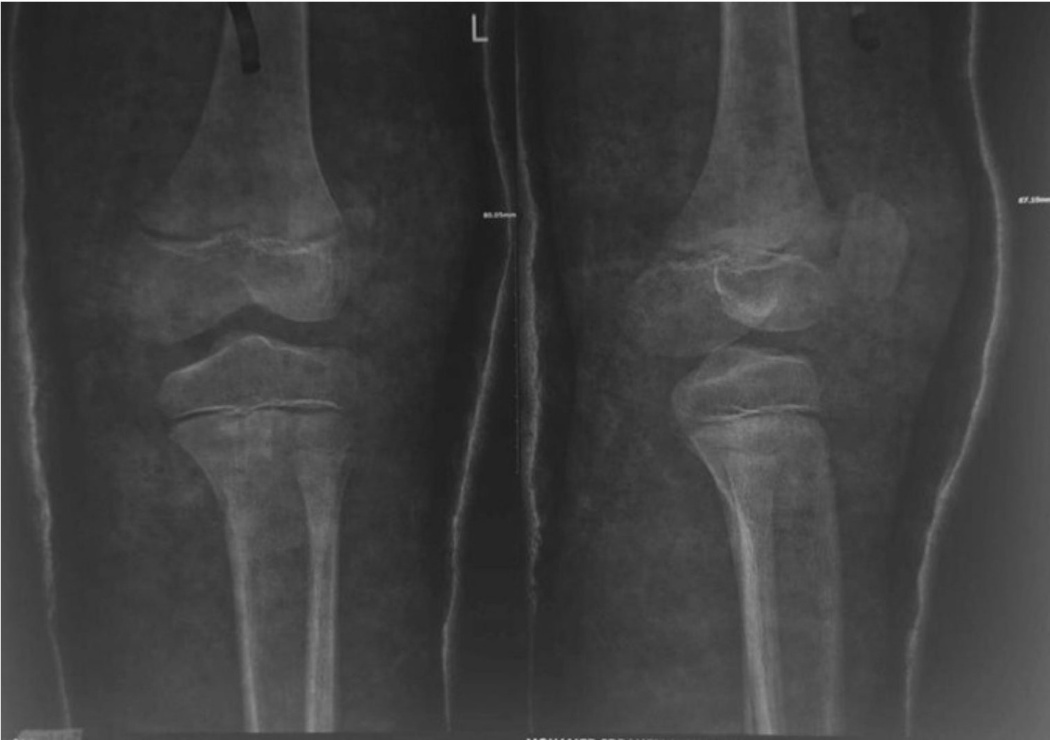

At the emergency room, radiographs were performed, which revealed a high-riding patella with a noticeable joint effusion as well as a small osteochondral fragment positioned distally to the patella. (Figure 2) As a result of the high-riding patella on the radiographs and the avulsion of the distal osteochondral side of the patella, a patellar sleeve fracture was detected. The surgery was scheduled for the next day.